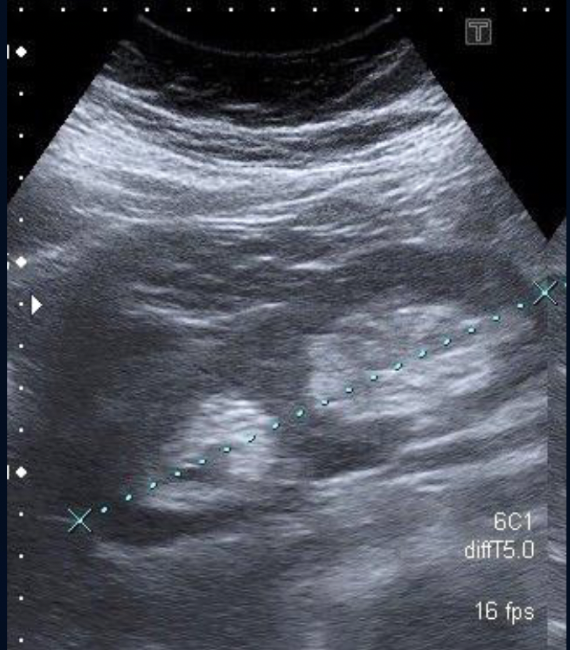

What is this?

Duplex Kidney